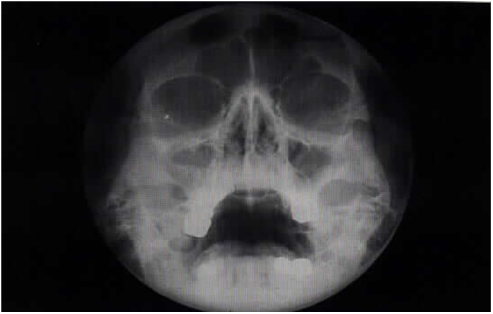

A case report these pictures of this page are about:maxillary tuberosity fracture complication. Maxillary tuberosity fractures during molar teeth extraction commonly occur in dental practice;

Applied anatomy maxilla is classification of fracture of maxilla rene le fort classification (1901). Maxillary tuberosity fracture associated with first molar extraction: A fracture of the maxillary tuberosity is a significant health problem.

A maxillary tuberosity fracture occurred and the decision was made to remove the tooth and the tuberosity as the segment appeared small.